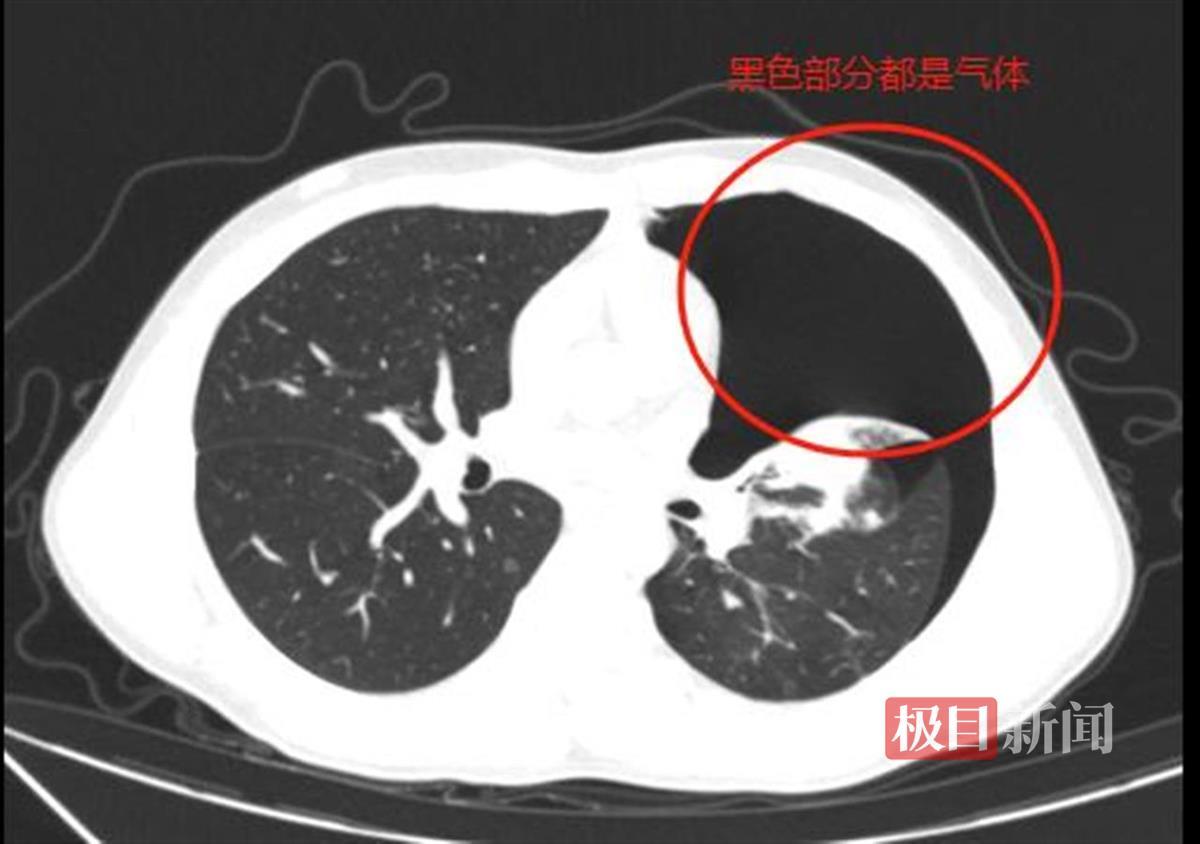

急诊科医生迅速为小江安排了胸部CT检查,结果显示,小江患有“左侧液气胸”,随后被收治到心胸外科继续治疗。CT影像显示多发肺大疱且气胸已压缩肺组织达50%以上,需立即进行穿刺排气。面对紧迫的病情,心胸外科主任王杰带领团队为小江实施了胸腔闭式引流术。术后,胸管通畅,成功引流出大量积气,症状暂时得到缓解。然而,由于小江肺上存在多发肺大疱,若不及时进行手术治疗,气胸极易反复发作,且二次发作时肺大疱再次破裂可能导致张力性气胸,严重时甚至可能危及生命。

CT影像显示,气胸已压缩肺组织达50%以上